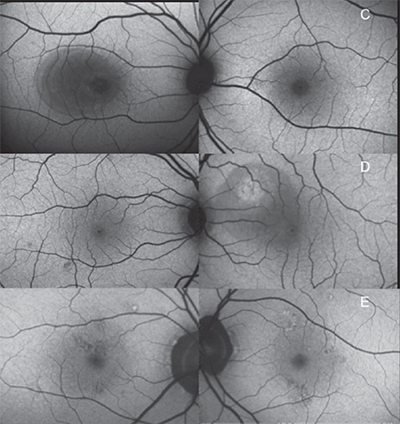

caffeine with bilateral central serous chorioretinopathy and high caffeine

intake: a 48-year-old male with a serous retinal detachment who consumed

a half-gallon of Mountain Dew per day (top); 30-year-old male with subretinal

fluid who drank six cans of Mountain Dew daily as well as supplemental

energy drinks (center); and a 53-year-old male with bilateral RPE changes who

consumed four to five cups of coffee per day (bottom).

Figure 2 shows fundus autofluoresence images of the macula of both eyes of patients with bilateral CSCR and high caffeine intake. The patient in Figure 2 top is a 48-year-old male who consumed a half gallon of Mountain Dew per day. He had central macular hypoautofluorescence from a serous retinal detachment in the right eye.

Figure 2 center shows a 30-year-old male who drank six cans of Mountain Dew per day as well as supplemental energy drinks. The right eye has small focal areas of macular hypoautofluorescence, and the left eye had hyperautofluorescence associated with serous retinal detachment

The patient in Figure 2 bottom is a 53-year-old male with bilateral irregular hyper- and hypoautofluorescent RPE changes who consumed four to five cups of coffee per day.